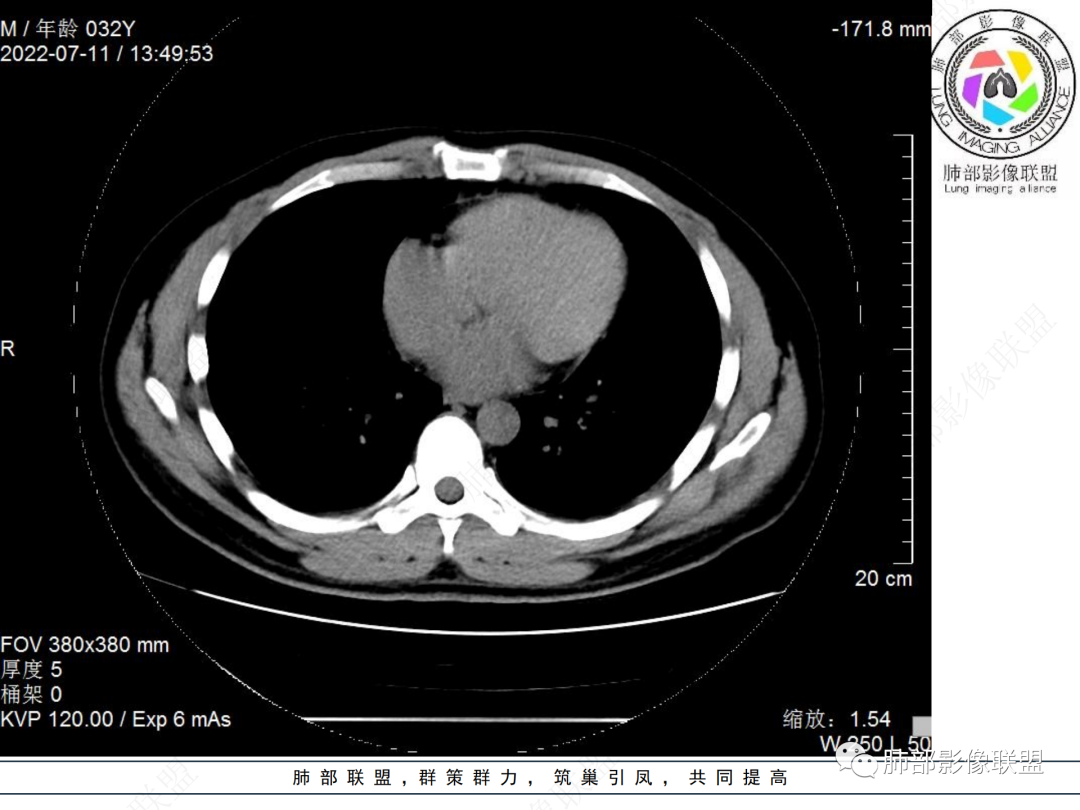

左肺下叶后基底段开口处结节,边缘光滑清楚,没有增强扫描,年轻男性患者痰血三天,考虑1.良性病变:腺瘤、错构瘤、平滑肌瘤

2.恶性:类癌、粘液表皮样癌。

左肺下叶外后基底段气管内见结节状影,边缘部分清晰。考虑错构瘤,待排恶性病变。

左肺下叶气管内外占位病变,咯血病史,考虑类癌,粘表待排。

青年男性,左肺下叶后基底段支气管开口软组织结节,边缘光整,气管镜提示质软,易出血,考虑类癌

左肺下叶后基底段开口处结节,边缘光滑清楚,年轻患者考虑鳞癌或腺样囊腺癌

左肺下叶气道腔内占位,远端无花花草草,疾病谱:鳞,类癌,粘表,腺样囊腺癌,小,无增强,不好判断,临床咯血,选类癌。

大支气管腔内结节,考虑类癌

左肺下叶后基底段开口处结节影,边缘光滑,患者年龄较小,首选类癌

男性,咳血左肺下叶支气管腔内结节影,没有阻塞性炎症,考虑类癌,鳞癌

年轻男性,支气管内结节,首先类癌

左肺下叶后基底段开口处腔内见壁结节,花生米样,宽基底,补充增强及矢状位重建,确定我无向壁外突破浸润生长,另见强化的特点,临床触之易出血,类Ca可能性大。

年轻男性,支气管腔内占位,边缘尚平整,年轻人,首先类癌,鉴别错构

年轻男性,咳血,左肺下叶后基底段支气管腔内结节,边缘光滑,首先考虑青年三件套,类癌大于粘液表皮样癌,支气管镜质软,触之易出血,鉴别血管瘤,平滑肌瘤

左肺下叶后基底段开口部结节,密度较均匀一致,边缘较光整,目测密度偏低,支气管镜示:质软、触之易出血,考虑恶性,类癌。

支气管腔内结节,有蒂与支气管壁连接,考虑良性病变可能性大,支气管错构瘤  血管瘤一类的

左肺下叶后基底段支气管腔内结节,有蒂,容易出血,先考虑良性病变,肉芽组织型血管瘤,与类癌鉴别。

青年男性,左肺下叶后基底段支气管开口软组织结节,边缘光整,气管镜提示质软,易出血,考虑恶性类癌

左肺下叶后基底段开口处结节影,边缘光整,年轻患者,伴咯血,考虑鳞癌,类癌不能排除